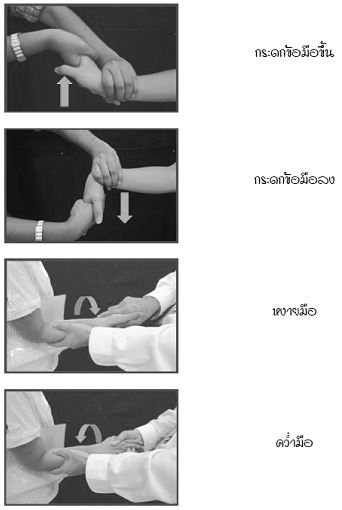

16 กันยายน 2557 04:39:26 #2 ความจริงคุณน่าจะปรึกษาคุณหมอที่รักษาอยู่ เพราะรู้พยาธิสภาพและสามารถให้คำแนะนที่เหมาะสม อย่างไรก็ดี ขอแนะนำวิธีการบริหารดังนี้ครับ การบริหารเพื่อเพิ่มองศาการเคลื่อนไหวของข้อมือ ดังนี้ การบริหารเพื่อเพิ่มความแข็งแรงของข้อมือ แขน และมือ ดังนี้ 1. เหยียดข้อมือและนิ้วมือเต็มที่ 2. กำมือและเกร็งกล้ามเนื้อมือและแขน 3. ดันมือและแขน ให้ประสานมือทั้ง 2 ข้าง ใช้มือข้างหนึ่งดันออก ส่วนมืออีกข้างหนึ่งดันเข้า เป็นการต้านแรงมือตนเอง ทำสลับข้างกัน 4. ยกน้ำหนัก เริ่มจากน้ำหนักน้อยๆ แล้วเพิ่มน้ำหนักมากขึ้น